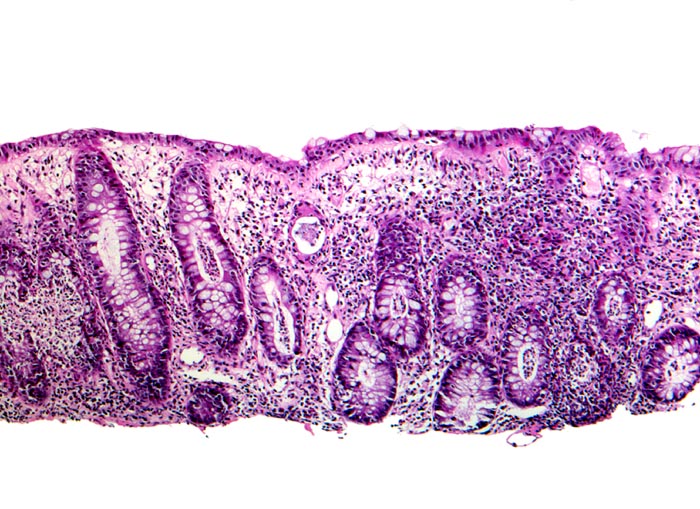

Infektiöse Kolitis

Akute Kolitis mit zahlreichen Kryptenabszessen und eitriger Kryptitis. Die Kryptenarchitektur ist weitgehend erhalten und die Anzahl Becherzellen kaum vermindert.

Histologie

50